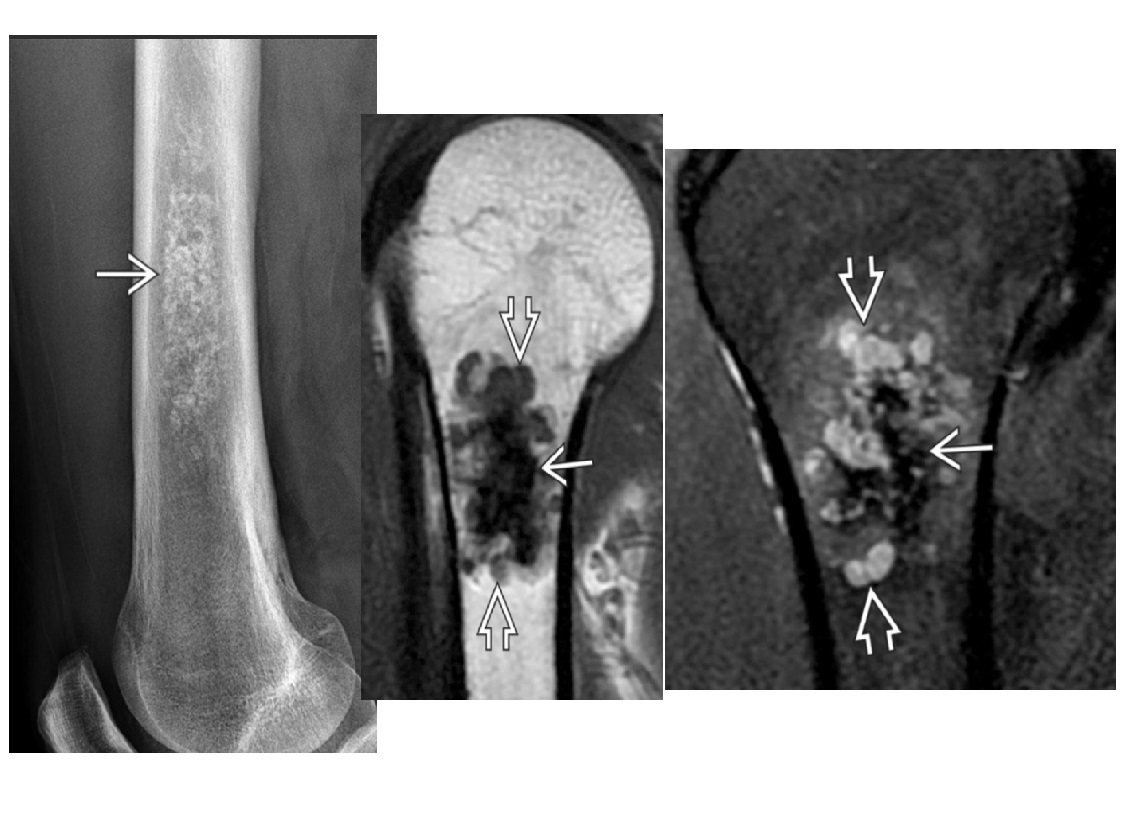

Adamantinoma

Low-grade, malignant lesion most frequently arising in tibial** cortex**

Mutlifocal

slcerotic and lytic compoents

*Cortically based lesion in anterior tibia